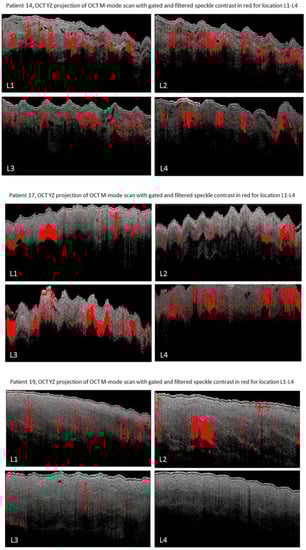

For patients 9, 14, 17 and 19 the speckle contrast analysis was possible on all four locations on the gastric tube. Figure 9 depicts the OCT M-mode scans of all four locations for patients 9, 14 17 and 19. A decrease of areas with speckle contrast indicative of flow (red) is visible towards the fundus in patients 9, 14 and 19. The expected shadowing due to multiple scattering [] caused by the high scattering coefficient in blood is clearly observed in the images [].

Figure 9.

OCT speckle contrast indicative of flow overlaid with OCT grayscale (YZ) images from M-mode scans from location 1 (L1, 3 cm below the watershed), location 2 (L2, watershed), location 3 (L3, 3 cm above the watershed), location 4 (L4, fundus). In patient 9 high speckle contrast indicative of flow is seen in location 2 on the watershed area. In patient 14 and 19 a decreased speckle contrast indicative of flow is observed towards location 4. In patient 17 an increase in speckle contrast indicative of flow from location 1 to 4 is observed.